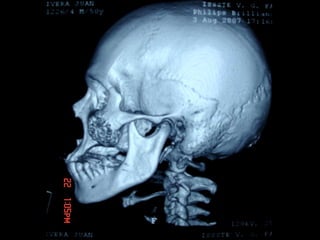

AmeloblastomaAmeloblastoma

Ameloblastoma

Neumólogo: Dr. Crescenciano González OlivaresNeumólogo: Dr. Crescenciano González Olivares

Trismus importante debido a queTrismus importante debido a que

El tumor ya rompió el hueso com-El tumor ya rompió el hueso com-

Pacto de la cara interna de laPacto de la cara interna de la

Mandíbula y empezó a tomar elMandíbula y empezó a tomar el

Músculo pterigoideo interno.Músculo pterigoideo interno.

Trismus importante debidoa queTrismus importante debido a que El tumor ya rompió el hueso com-El tumor ya rompió el hueso com- Pacto de la cara interna de laPacto de la cara interna de la Mandíbula y empezó a tomar elMandíbula y empezó a tomar el Músculo pterigoideo interno.Músculo pterigoideo interno.